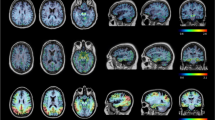

Voxel-wise analyses across all subjects showed significant associations between widespread cortical [18F]flortaucipir binding (right > left binding) and CSF p-tau. In SCD subjects, associations between tau PET and CSF p-tau were mainly observed in temporoparietal regions, whereas in MCI/AD this association was observed in the fronto-temporo-parietal areas (Fig. 2). All results survived family-wise error corrections, except for the results in the MCI/AD group. CSF t-tau showed a comparable, although marginally more widespread pattern than p-tau (Supplementary Fig. 2).

Voxel-wise associations between CSF p-tau and [18F]flortaucipir BPND (top row) and SUvr (bottom row). Voxel-wise associations are shown using a threshold puncorrected < 0.001(red) and pFWEcorrected < 0.05 (blue) at the voxel level. Contrasts were adjusted for age, sex, and time lag between LP and [18F]flortaucipir PET scan. The associations were assessed in the total sample, within SCD subjects only and within MCI/AD subjects only

Although SUVr overestimated BPND values (Table 1), comparable results were obtained for SUVr and BPND. Overall, higher p-tau was related to higher entorhinal (sβ = 0.50), limbic (sβ = 0.47), and neocortical (sβ = 0.43) [18F]flortaucipir SUVr, all p < 0.01 (Table 2). In line with BPND, within groups, correlations were stronger for SCD subjects, and strongest correlations were seen in the limbic region (sβ = 0.67 p < 0.01, Table 2, Fig. 1). Voxel-wise analysis confirmed comparable associations between [18F]flortaucipir BPND or SUVr and CSF p-tau (Fig. 2), and the associations with cognition and atrophy were essentially the same for SUVr (Supplementary Tables 7, 8) and BPND (Tables 3 and 4).